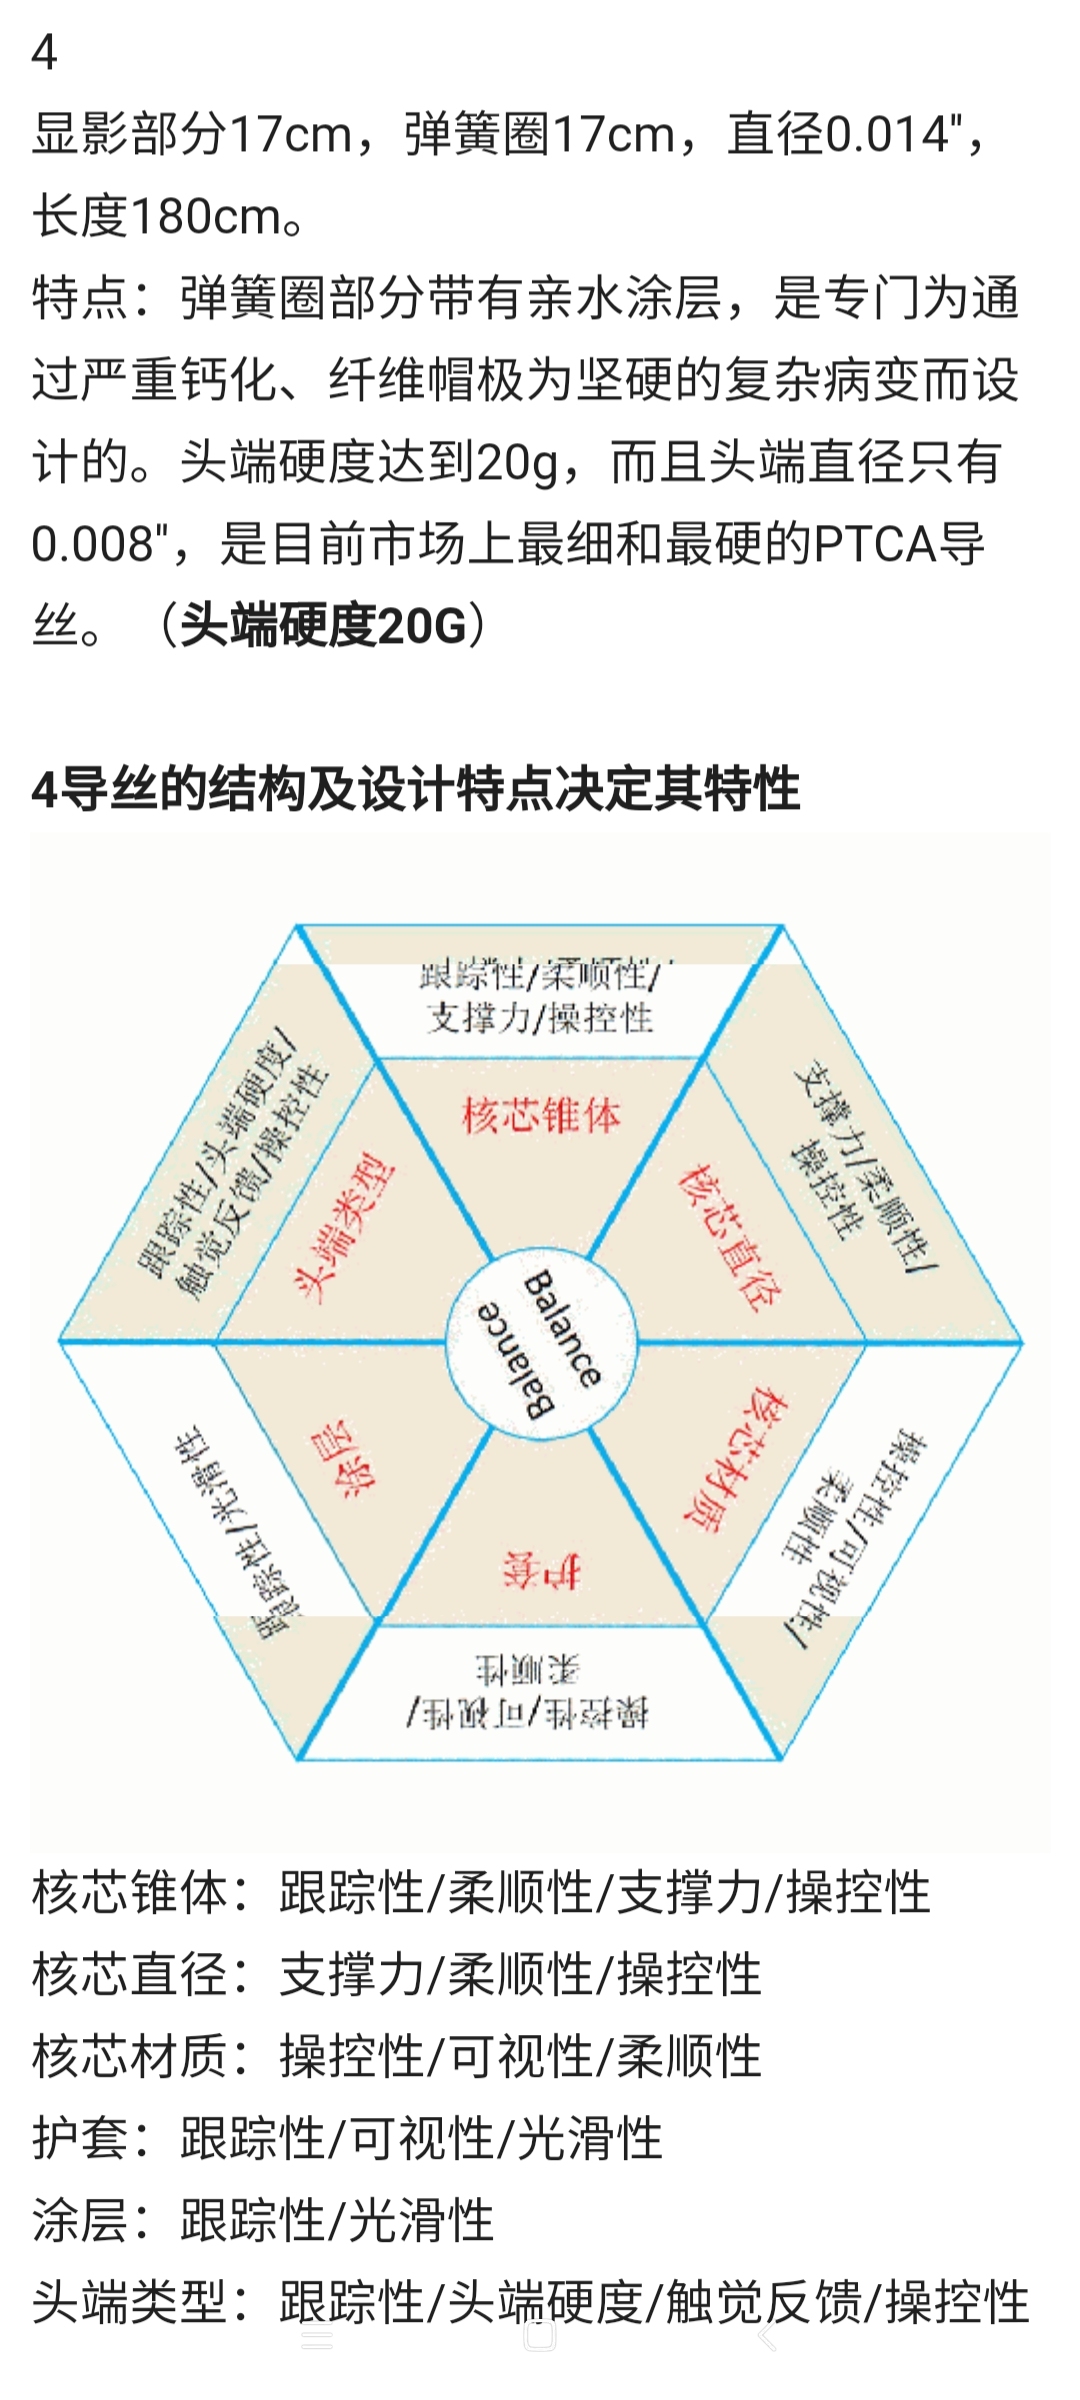

备好心心念的Conquest Pro 8-20,准备开干

双通道

股动脉8F导引导管

桡动脉6F导引导管

望远镜技术

6F导引导管(支撑)+125多功能造影管(支撑+导向)+动脉瘤导管(小支撑)+Conquest导丝(开通利器)

艰苦卓绝的吃线过程,此处心中浮现出一万个草泥马,最终,多角度+超选造影,验证真腔